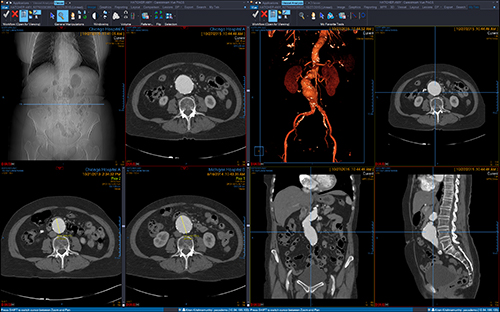

撮影画像の参照から,3Dデータの表示・解析までを実現する読影対応の「Vue PACS Client」は,自動位置合わせ,病変管理や,多数の解析機能で読影医をサポートします。臨床機能としては,PET/CTやCTパフュージョン解析,MRディフュージョン解析,マンモグラフィのトモシンセシス読影といった機能を搭載。効率的なPACS読影ワークフローをご提供します。